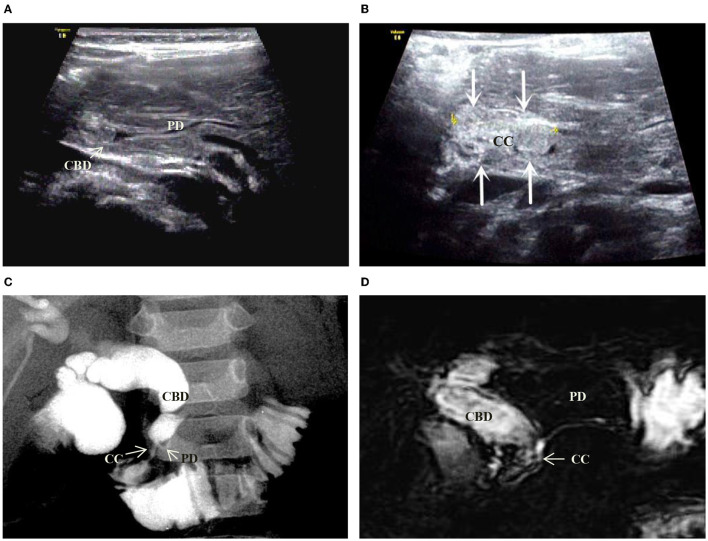

On the basis of the new JSPBM’s classification, the individual morphologic features of PBM were described as four types (ref. 11) in presenting our ultrasound report: type A (stenotic)—the distal CBD with stenosis before joining with the CC, and an angle of slightly < 90° usually observed in the conjunction between PD and CBD at a site distant from the papilla of Vater; type B (non-stenotic)—the distal CBD emerging but without stenosis pattern before joining with the CC, in addition, an approximately right angle customarily seen in the conjunction between PD and CBD at a site distant from the papilla; type C (dilated channel)—the dilated CC significantly occurred; type D (complex)—a complicated configuration in PBJ contexture including the PD, the terminal portion of the CBD, and the dilated accessory PD, and one end opening as a small nipple in the duodenum and the other end converged with the CBD downward into the CC. Figures 1–4 show the representative imagines of A, B, C, and D types of PBM, respectively.

Among the 31 cases, 14 cases were stenotic type (A), 11 cased were non-stenotic (B), and five were dilated channel (C). The complex type (D) rarely occurred and only one case was found in our medical center. Table 3 shows the comparison among A, B, and C types in terms of gender, age, the maximum internal diameter of CBD, the internal diameter of CC, the length of CC, the internal diameter of the main PD, and the thickness of the gallbladder. Type A causes a significant increase in the internal diameter of CBD. Type C appears significant increases in internal diameter and length of CC and internal diameter of PD.